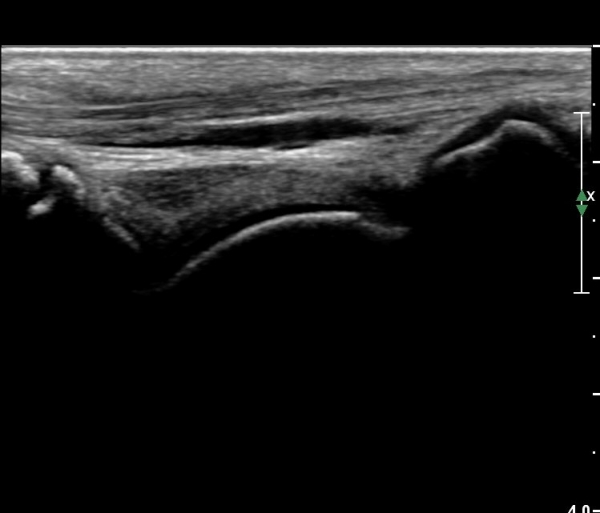

Àü°ÅºñÀδë Á¾´Ü¸é°Ë»ç¿¡¼­ ¾È´ë ºñ°ñ ºÎÂøºÎÀÇ Àú¿¡ÄÚ ºÎÁ¾°ú ºÎºÐÆÄ¿­ÀÌ °üÂûµÈ´Ù(»çÁø 4).

Àü°ÅºñÀδë Á¾´Ü¸é°Ë»ç¿¡¼­ Àü°ÅºñÀδëÀÇ Àú¿¡ÄÚ ºÎÁ¾ÀÌ °¨¼ÒÇϰí ÀδëÀÇ ¿¡ÄÚ°¡

Áõ°¡µÇ¾ú´Ù(»çÁø 3, 4).

Àü°ÅºñÀδë Á¾´Ü¸é°Ë»ç¿¡¼­  Àú¿¡ÄÚ ºÎÁ¾ÀÌ °¨¼ÒÇϰí ÀδëÀÇ ¿¡ÄÚ°¡ Áõ°¡µÇ¾ú´Ù(»çÁø 2, 3, 4).